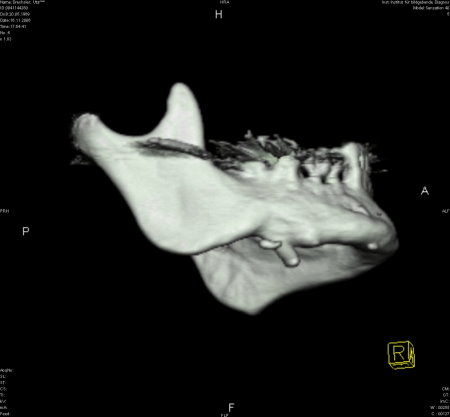

Zur genauen Planung der Kieferkorrektur wurde ich zum CT geschickt. Aus den scheibchenweisen Bildern setzte der Computer ein dreidimensionales Bild zusammen. Dabei ist auch sehr deutlich dieses verlagerte Knochenstück zu sehen.

Zwischenzeitlich stand auch mal die Überlegung im Raum, eine Kinnplastik durchzuführen, bei der die Kinnspitze abgesägt und danach im "richtigen" Winkel wieder aufgesetzt wird. Das klang natürlich auch erst mal ein bissel erschreckend - aber schließlich zählt das Ergebnis. Nach Auswertung der 3-D-Annimation wurde dann allerdings "nur" die erstbeschriebene Kieferkorrektur durchgeführt.